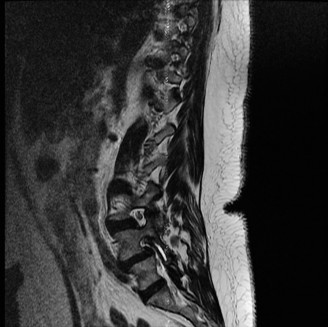

CASE 1 A 63-year-old male sustained a hyperextension injury to his neck while diving into a pool. Upon presentation, he reports decreased sensation in his hands and decreased strength in his arms and wrists, but no lower extremity complaints. On motor examination, he has 5/5 strength in his deltoids and elbow flexors and 4/5 strength in the elbow extensors, wrist extensors, and finger flexors. Lower extremity motor examination is normal. Sensation is decreased to light touch in both hands. Otherwise his sensation is preserved. Images of his cervical spine are shown in Figures 1–1 to 1–3.

Figure 1–1

Figure 1–2

Figure 1–3

The correct answer is (B). The clinical scenario describes a patient with central cord syndrome (CCS). CCS continues to be the most common incomplete spinal cord injury accounting for 15.7% to 25% of all spinal cord injuries. The characteristic presentation is an extension moment injury in a previously spondylotic and stenotic spine. Figures 1–1 to 1–3 demonstrate a spondylotic spine with central narrowing and CSF effacement that is worst at the C3–4 level. Bleeding, edema, and/or Wallerian degeneration lead to damage of the lateral corticospinal tract which is the main descending motor tract in the spinal cord. The more central anatomic position of the homunculus to the upper extremities places them at greater risk than those to the lower extremities. As such, injury to the lateral corticospinal tract is characterized by upper more than lower extremity involvement and motor deficits being more pronounced than sensory deficits.